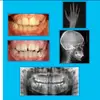

دكتورة ميرفي قيشلا طبيبة أسنان

مجالات التخصص

طبيب أسنان